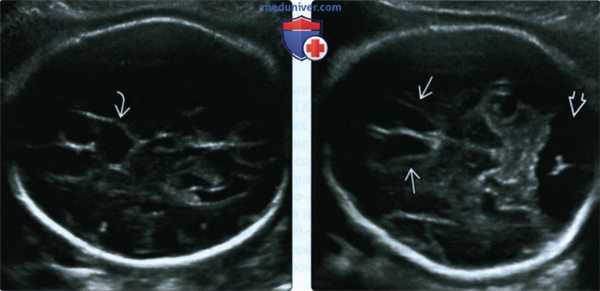

о Боковые желудочки разделены и параллельны (на аксиальных срезах), признаки «головы быка», «трезубца», «шлема викинга» или «головы лося» (на корональных срезах)

о На аксиальных срезах ключевым для постановки диагноза является состояние боковых желудочков

- Параллельные и разделенные

- Преддверие/затылочный рог бокового желудочка часто расширен («кольпоцефалия»)

о Корональные срезы:

- Межполушарная борозда спускается вниз до крыши III желудочка

- Пучки Пробста: медиальные парасагиттальные тракты белого вещества, светлее других миелиновых структур на Т1-ВИ, зазубривают боковые желудочки («голова быка» и т.д.)

- Височные рога расщеплены, гиппокамп закруглен

о Аксиальные срезы:

- Параллельные разделенные боковые желудочки, кольпоцефалия

о В аксиальной плоскости: отсутствует ППП, желудочки имеют форму слезы (кольпоцефалия), параллельно расположенные боковые желудочки

о Фронтальная плоскость: отсутствует ППП, передние рога боковых желудочков напоминают по форме рога быка, мозолистое тело не визуализируется

о Кольпоцефалия: расширение треугольников и затылочных рогов

• Желудочки в форме слезы

• Медиальная стенка желудочка сильнее всего отклонена от средней линии в области переднего рога:

о Боковые желудочки расположены на большом расстоянии друг от друга, параллельны

о Многочисленные описания строения желудочков:

- Треугольные, в форме рогов быка, шлема викинга, головы лося, техасского лонгхорна

о Заметная межполушарная щель

о III желудочек расположен выше, чем в норме:

- Соприкасается с межполушарной щелью спереди

- Лучше всего визуализируется во фронтальной плоскости

о Основной признак - отсутствие ППП: важно не перепутать ППП со столбами свода мозга:

- ППП должна представлять собой анэхогенную структуру в форме коробки, лежащую между передними рогами боковых желудочков по средней линии

о Извилины:

- Отсутствует поясная извилина

- В сагиттальной плоскости извилины расходятся радиально и выглядят как лучи солнца или спицы колеса

- «Лучи» сходятся к III желудочку